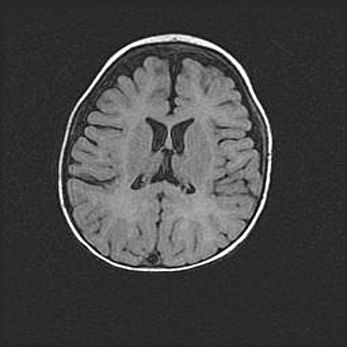

Сообщающаяся гидроцефалия. Кистозная энцефаломаляция головного мозга.

Возраст: 3 месяца 4 дня

Вес: 3100 г

Пол: женский

Окружность головы: 34 см

Срок гестации: 31 неделя

Кистозная энцефаломаляция головного мозга - одна из форм поражения головного мозга в детском возрасте. Характеризуется возникновением множественных и распространённых кист в коре, белом веществе и подкорковых образованиях головного мозга у плодов, новорождённых и детей раннего возраста. Развитие кистозной энцефаломаляции связано с внутриутробной асфиксией и гипотонией, родовой травмой, тромбозом синусов, пороками развития сосудов, инфекциями, сепсисом и другими причинами. Наиболее значимые инфекционные агенты: вирусы простого герпеса, цитомегалии, краснухи, токсоплазмы, энтеробактерии, золотистый стафилококк и другие.